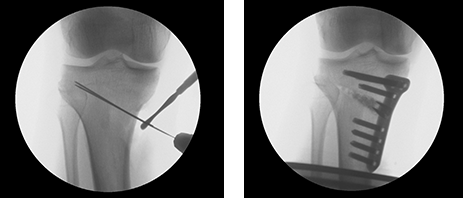

근위경골절골술은 오다리 변형으로 인해 무릎 안쪽 관절에 집중되는 체중 부하를 교정하기 위한 수술입니다.

무릎 아래 뼈인 경골의 정렬축을 조정하여, 이를 통해 무릎 안쪽 연골에 집중되던 부담을 줄이고 통증 완화를 기대할 수 있습니다.

마치 오래된 자동차 타이어에 편마모가 생기면 위치를 교환하여 사용 수명을 늘리는 것과 같은 원리입니다.